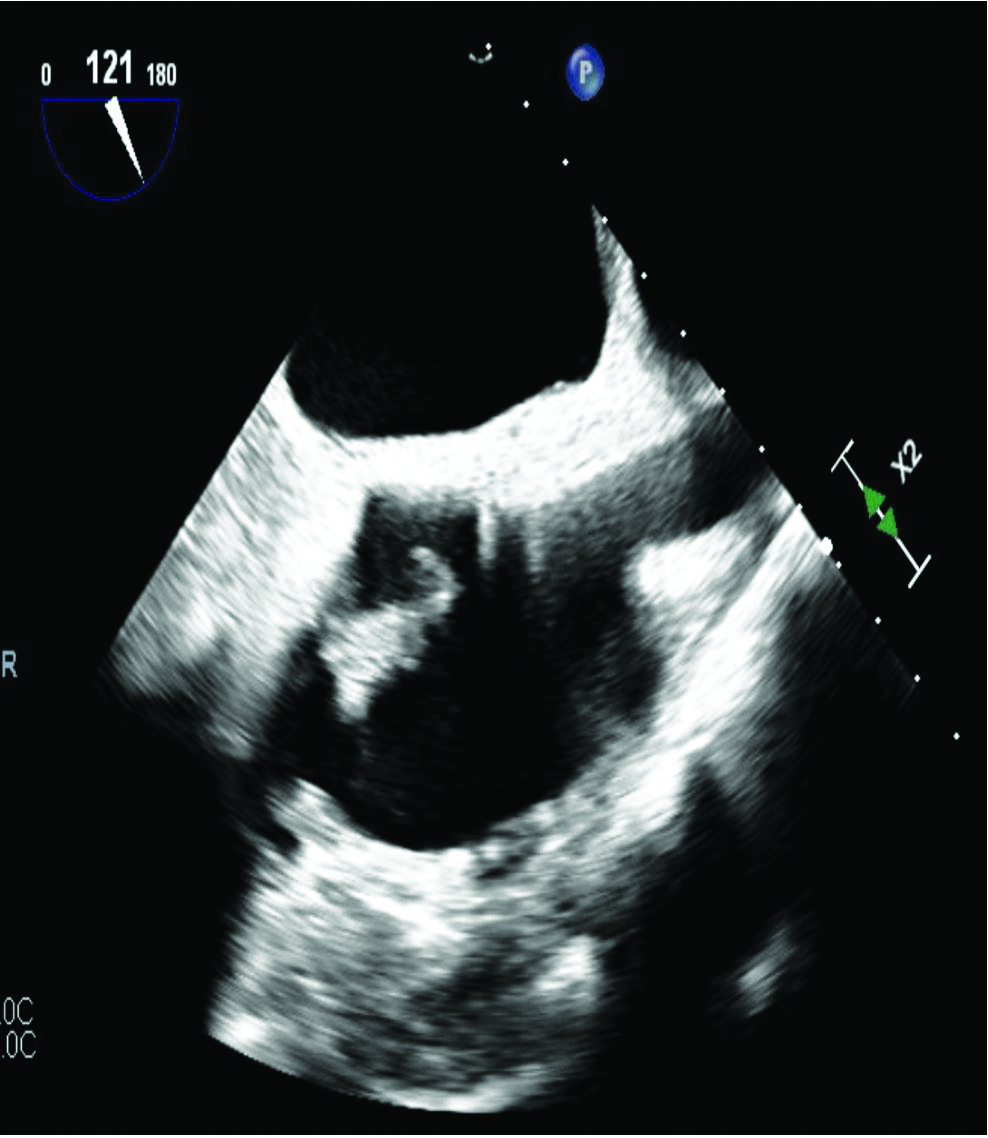

An African-American man, age 56, initially presented to the hospital due to fluid draining from his pacemaker site, fever, chills, and diarrhea. He had a history of hypertension, diabetes mellitus, chronic kidney disease, heart failure with reduced ejection fraction, and recurrent implantable cardio-defibrillator infections. On initial work-up, he tested positive for Clostridium difficile colitis, and the blood culture grew Pseudomonas aeruginosa. Subsequently, he underwent the lead extraction procedure during which residual vegetations of 3.0 × 1.5 cm on the atrial aspect of the tricuspid valve and 1.5 × 1.2 cm on the ventricular aspect were identified by trans-esophageal echocardiography (TEE) (Figure 3). A decision was made to use a minimally invasive approach for removal of the vegetations with AngioVac assistance, due to his co-morbidities making him a high-risk surgical case. The purpose of this procedure was to decrease the vegetation burden to reduce further septic embolization and to allow better penetration of antibiotics into the remaining infection. An access was obtained at the right common femoral vein and the right internal jugular vein (IJV). The first venotomy was serially dilated followed by placement of a 19 Fr reinfusion cannula through the IJV. The second venotomy was serially dilated followed by placement of a Gore 26 Fr dry seal sheath into the inferior vena cava. The AngioVac circuit was connected, and the AngioVac Catheter was advanced into the right atrium. The circuit was then begun, and debulking of the vegetations was performed. The trans-esophageal echocardiography showed a significant reduction, greater than 80%, in the size of the vegetations (Figure 4). The AngioVac system was stopped, and filtered blood without bacteria was returned to the patient by perfusion. Post-operatively, no complications were noted, and the patient left the operating room in stable condition.

Figure 3

Figure 3. TEE before procedure. Vegetations on tricuspid valve: 3.0 × 1.5 cm and 1.5 × 1.2 cm.

Figure 4

Figure 4. TEE after procedure. Significant reduction (>80%) of vegetations post-procedure.